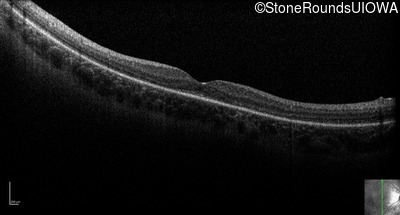

Optical Coherence Tomography - Right - 20/50

Exemplar